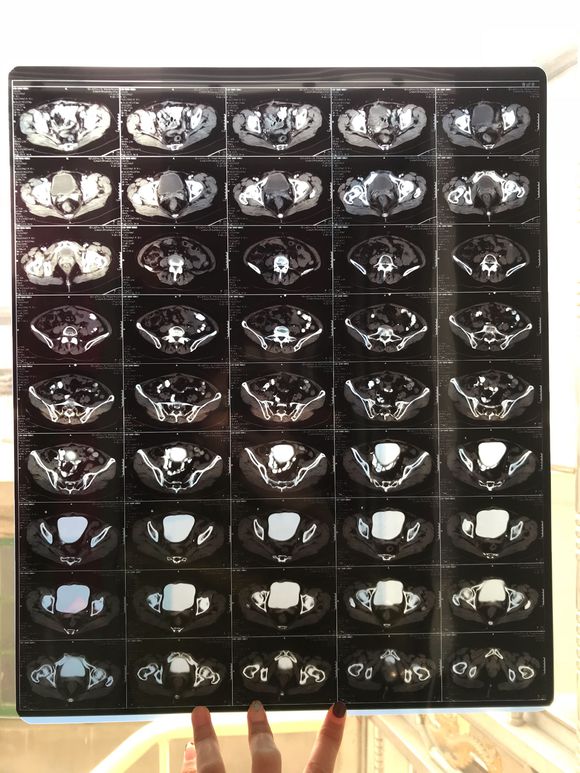

和你的故事 02019-04-09 患者家属我妈妈的病理结果报告,3期c1,大家可以帮忙看看吗,跪求了!我很急,谢谢!想知道是否严重,目前等术后出院后去肿瘤医院...

0人关注 4个回复 3467次浏览 -